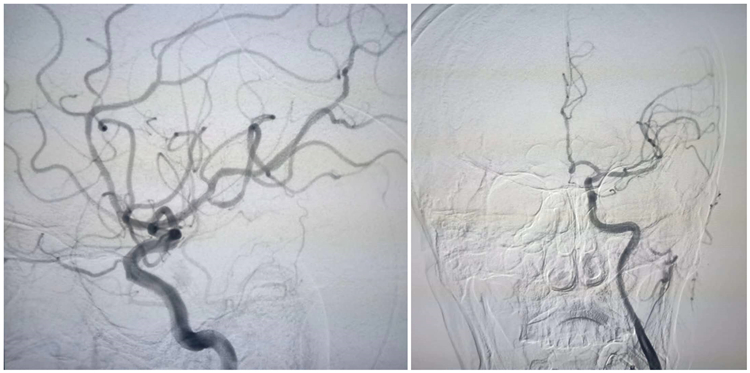

患者男,69岁,活动中摔倒,突发意识不清,肢体活动不灵2.5小时,考虑左侧颈内动脉血栓形成,我院急诊卒中中心开通绿色通道,DNT时间25分钟,给予静脉溶栓,同时推入导管室,在静脉溶栓桥接机械取栓过程中,血栓经造影冲刷至大脑前动脉A1段,血流mTICI 3级,现患者意识清楚,肢体肌力恢复。